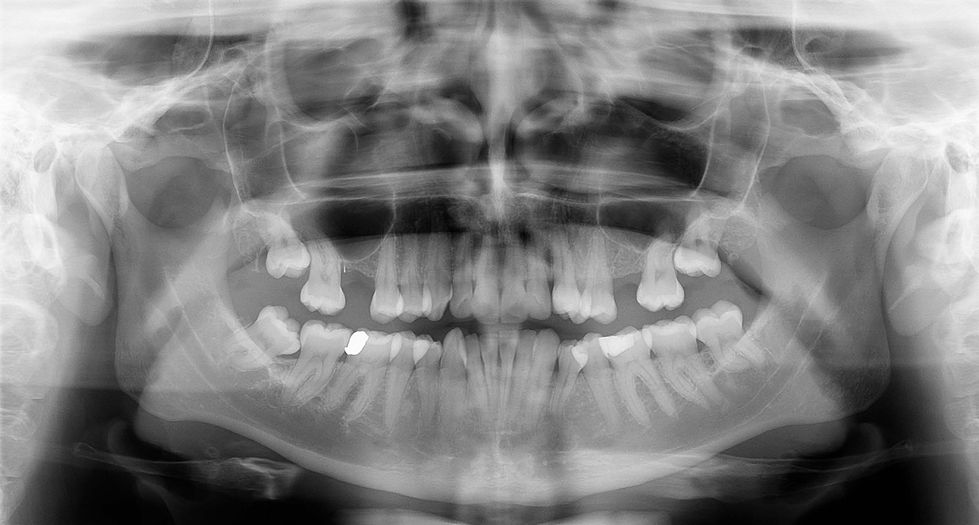

Smile (2021-2)

In progress

Documentation of my smile correction process. The developing work includes video, medical photography and models, mouth molds and extensive reflections on smiling, class, advertising, and beauty standards.